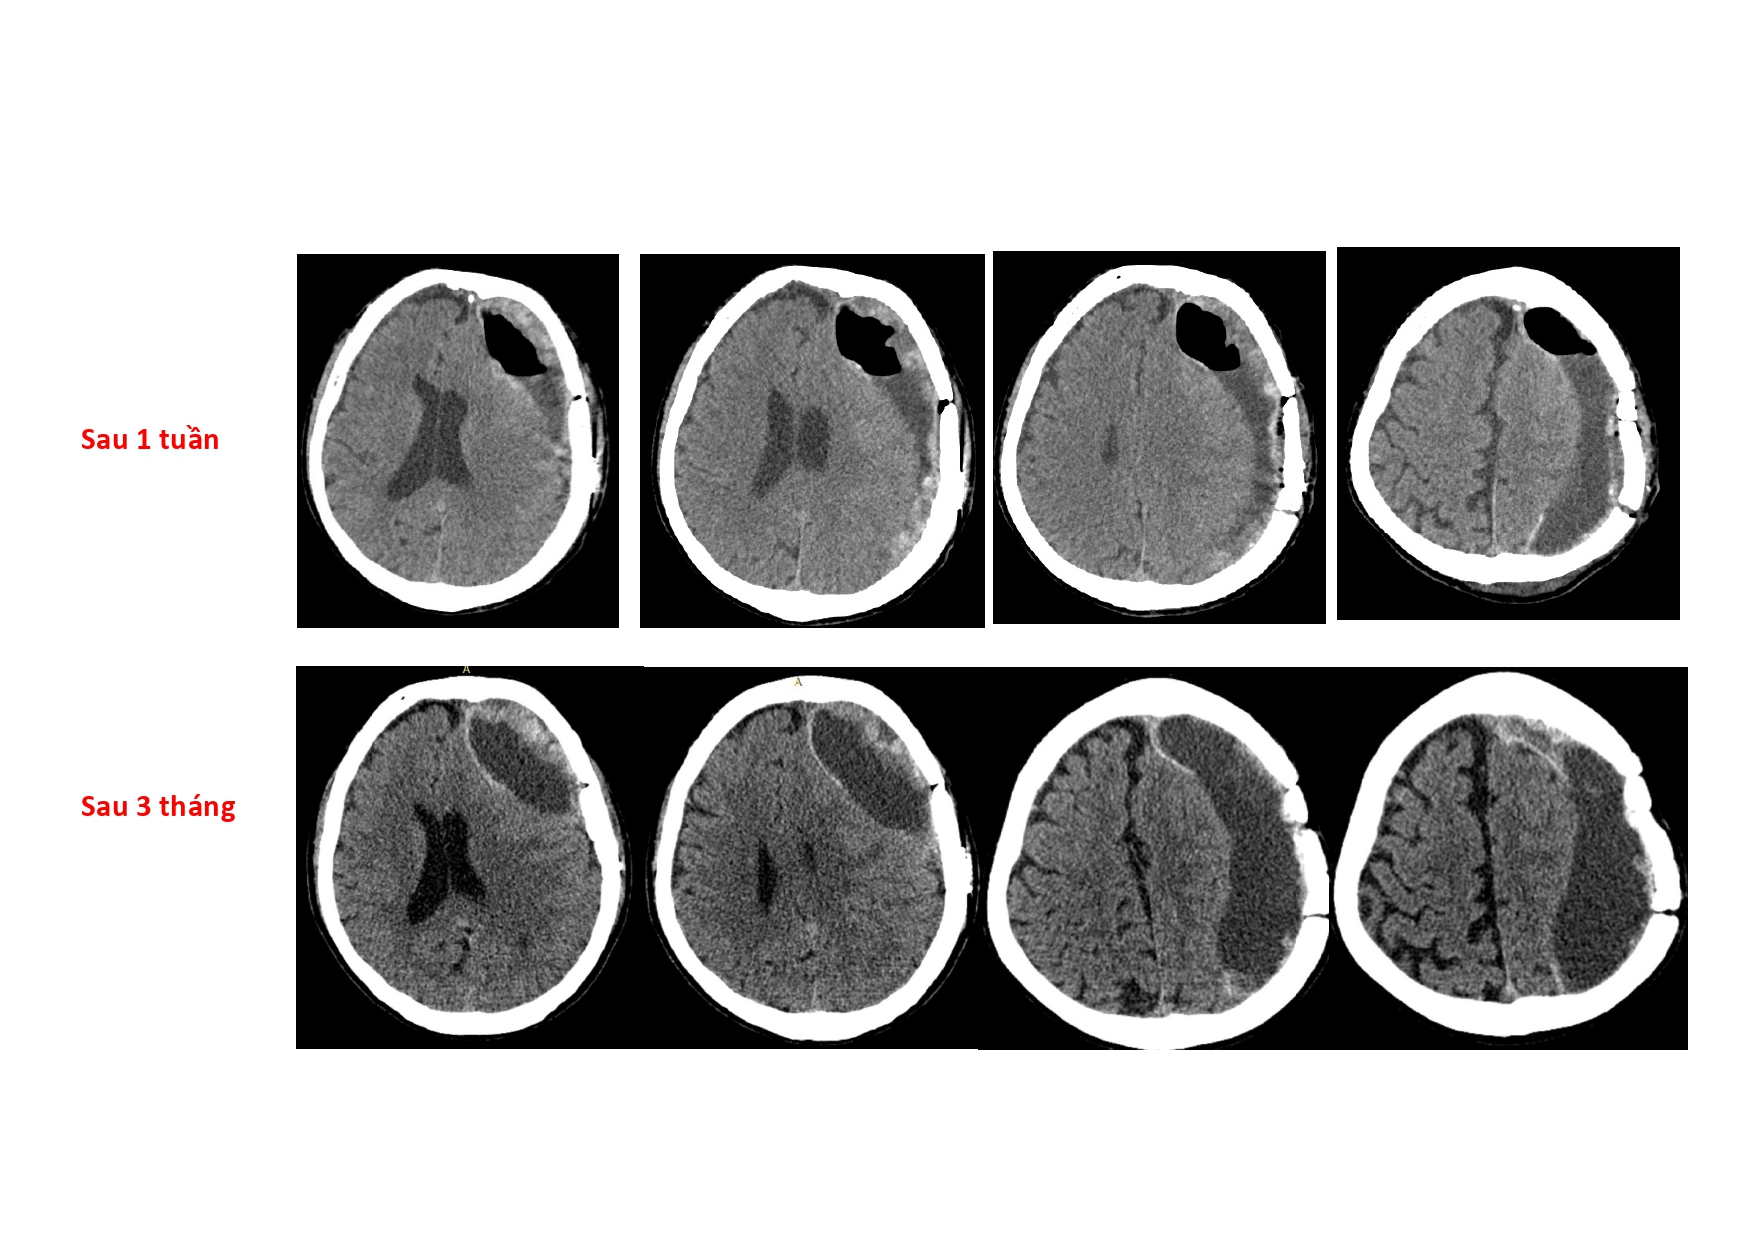

| 14:10 - 15:10 | DEBATE 2 | Recurrent chronic subdural hematoma– surgical or endovascular intervention? Surgical: Assoc. Prof. Duong Dai Ha Endovascular: Assoc. Prof. Le Thanh Dung | Moderator: Prof. Christian Matula Assoc. Prof. Duong Dai Ha | |